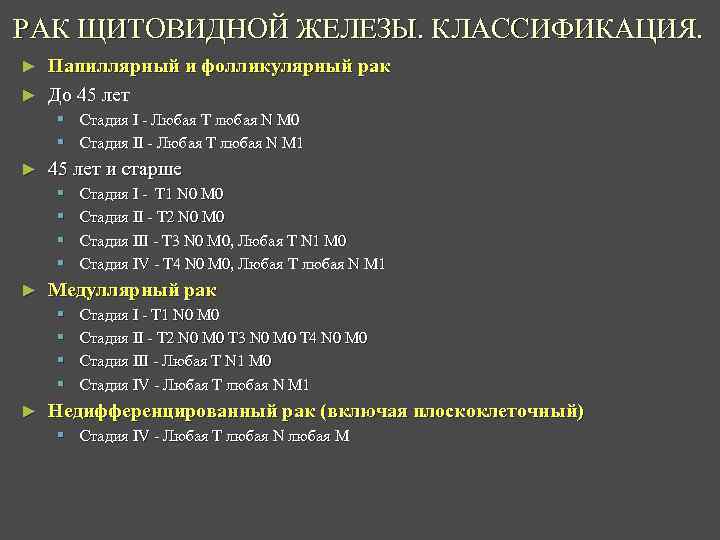

РАК ЩИТОВИДНОЙ ЖЕЛЕЗЫ. КЛАССИФИКАЦИЯ. Папиллярный и фолликулярный рак ► До 45 лет ► § Стадия I - Любая T любая N M 0 § Стадия II - Любая T любая N M 1 ► 45 лет и старше § § ► Медуллярный рак § § ► Стадия I - T 1 N 0 M 0 Стадия II - T 2 N 0 M 0 Стадия III - T 3 N 0 M 0, Любая T N 1 M 0 Стадия IV - T 4 N 0 M 0, Любая T любая N M 1 Стадия I - T 1 N 0 M 0 Стадия II - T 2 N 0 M 0 T 3 N 0 M 0 T 4 N 0 M 0 Стадия III - Любая T N 1 M 0 Стадия IV - Любая T любая N M 1 Недифференцированный рак (включая плоскоклеточный) § Стадия IV - Любая T любая N любая M